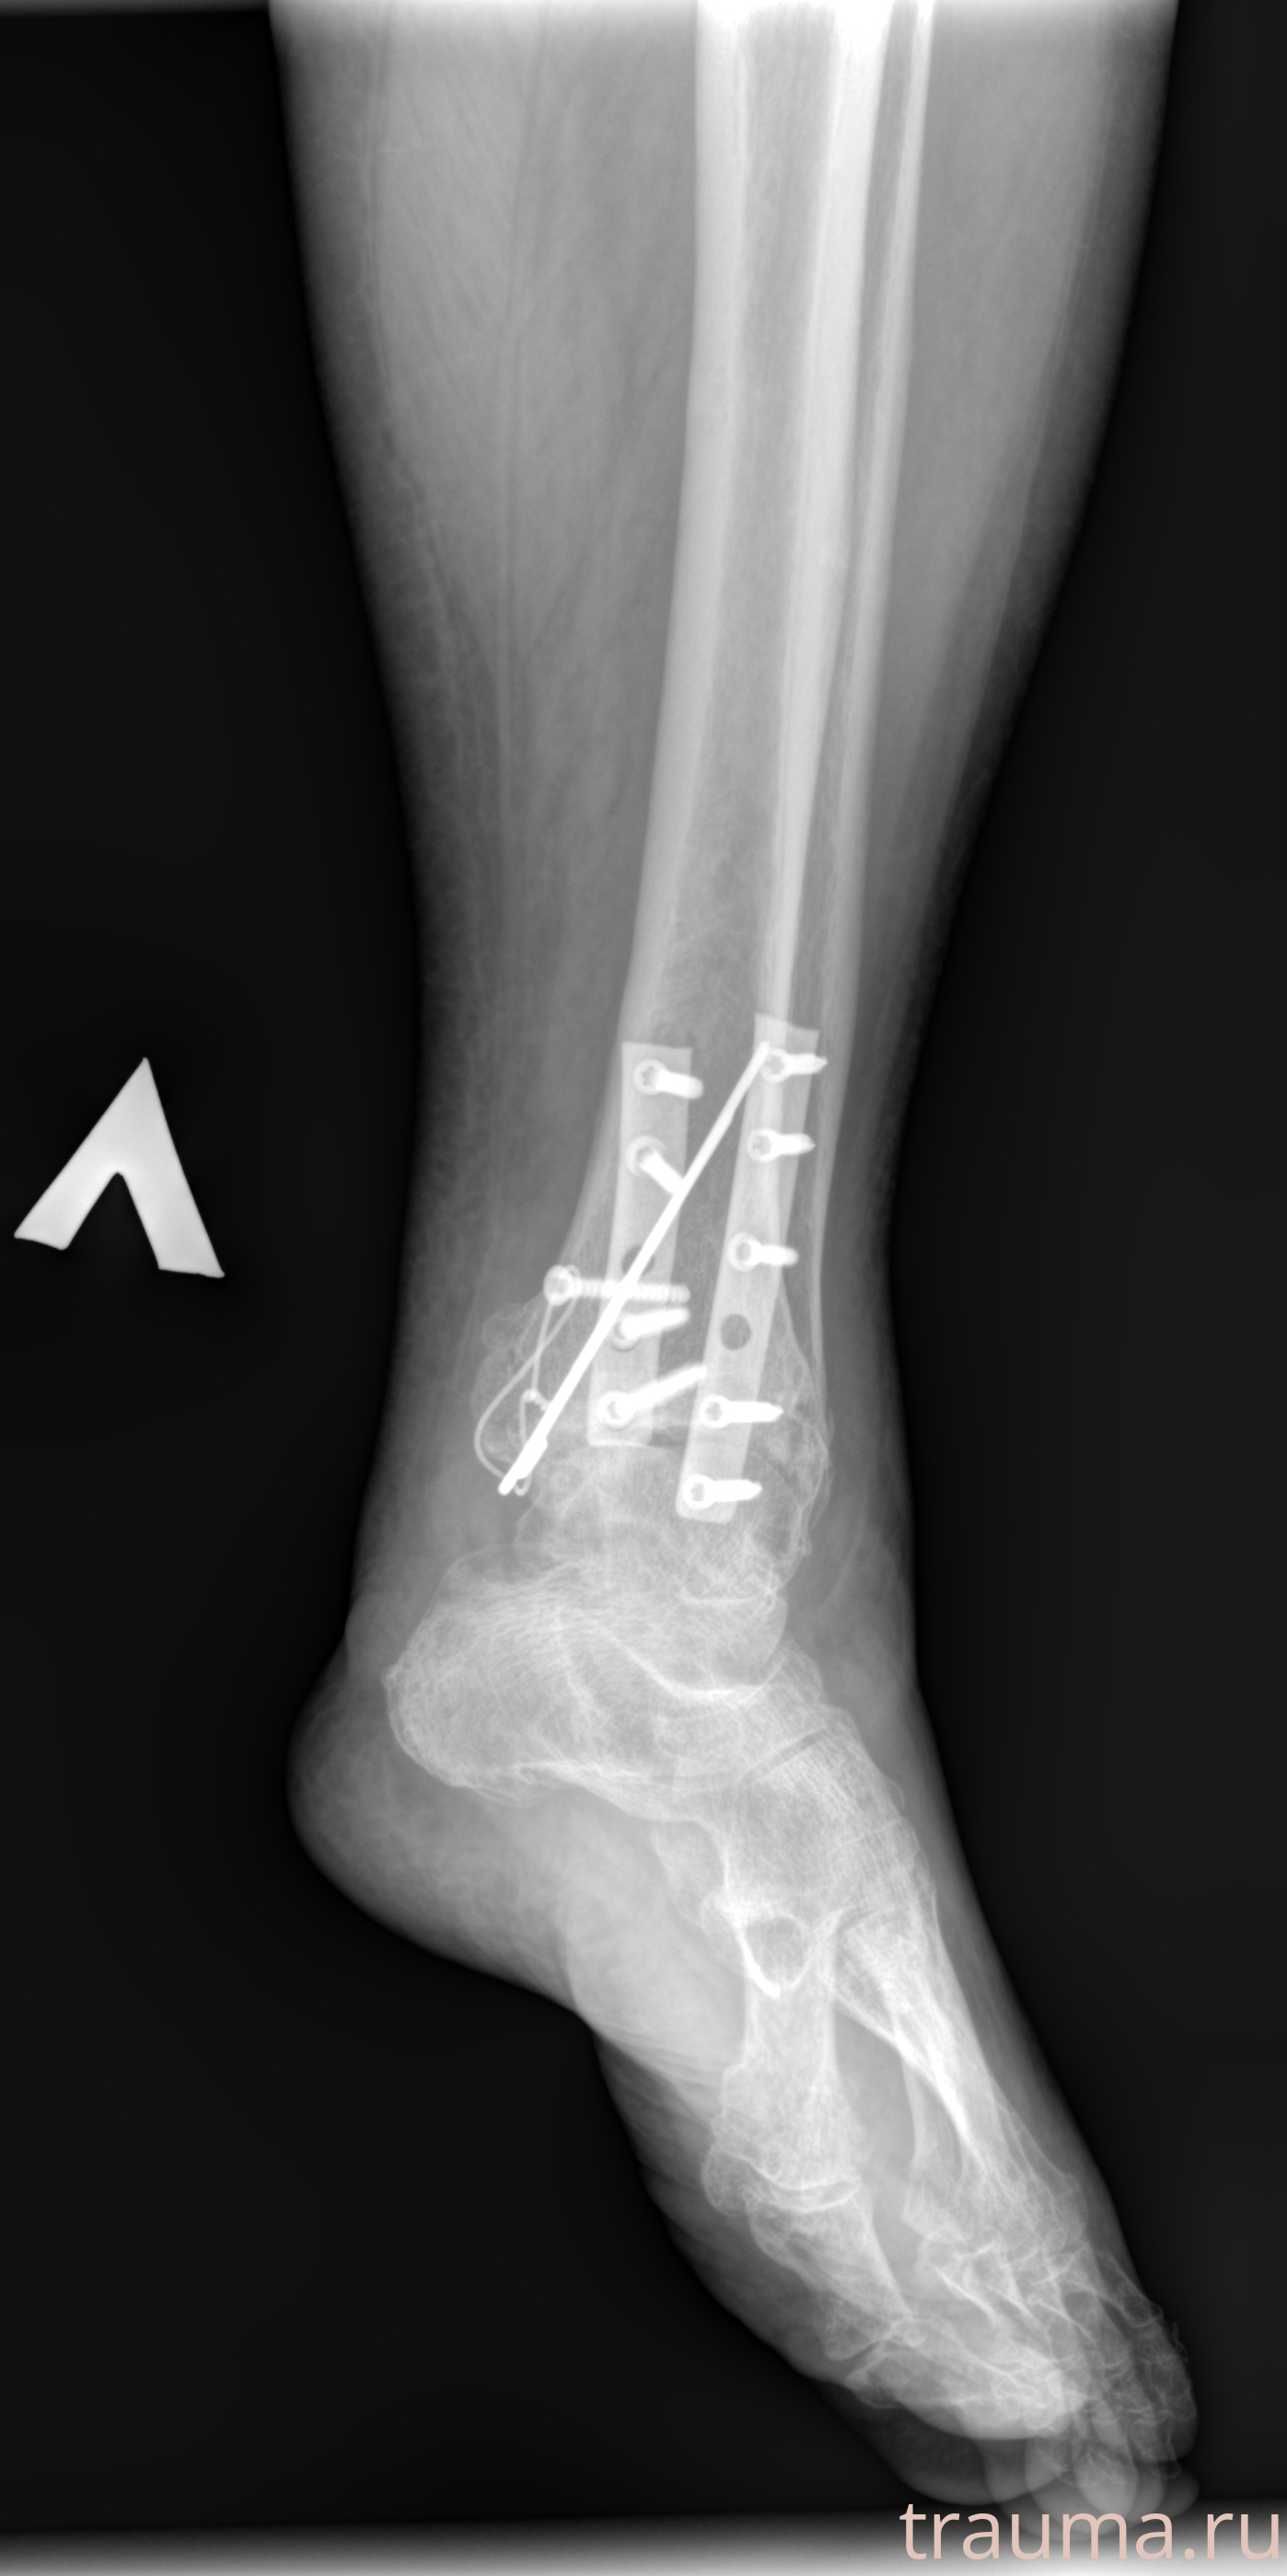

Рентгенограммы